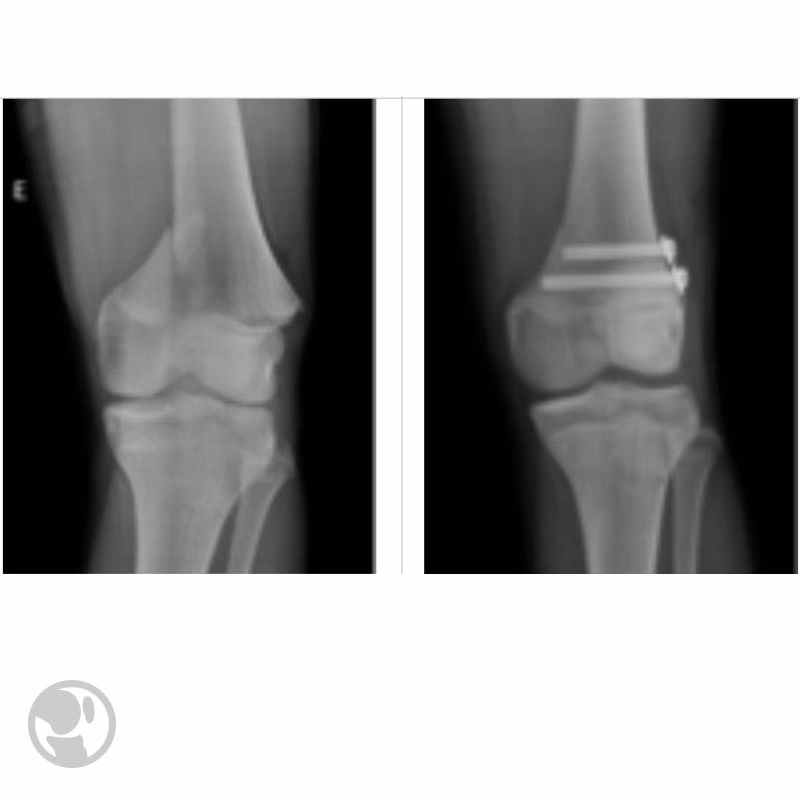

Se ha documentado el caso de un paciente varón de 15 años que, un año después de sufrir un traumatismo en el tobillo izquierdo (una epifisiolisis tipo II de Salter y Harris no desplazada en la tibia distal, tratada ortopédicamente con éxito), desarrolló gonalgia, limitación funcional y una deformidad de la rodilla izquierda en genu recurvatum. Las radiografías y una resonancia magnética revelaron un genu recurvatum óseo de 25° y un cierre fisario anterior de la tibia proximal izquierda, con la fisis prácticamente cerrada en comparación con la rodilla contralateral. Esto indicaba una epifisiodesis (cierre prematuro de la fisis) de la tibia proximal.

El paciente fue sometido a tratamiento quirúrgico, consistente en una osteotomía supratuberositaria tibial con una cuña ósea de adición de homoinjerto, que permitió restaurar la altura de la meseta tibial y elevar la rótula. Este caso subraya cómo una agresión a la fisis, incluso en una zona distante (tobillo) o de origen desconocido, puede tener repercusiones significativas en el crecimiento y la alineación de otras articulaciones, destacando la necesidad de una valoración exhaustiva por parte del especialista.